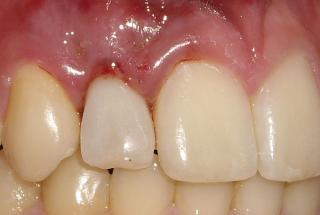

Clinical cases

MPI closely monitors clinical cases in the market to ensure their correct functioning and successful outcome.